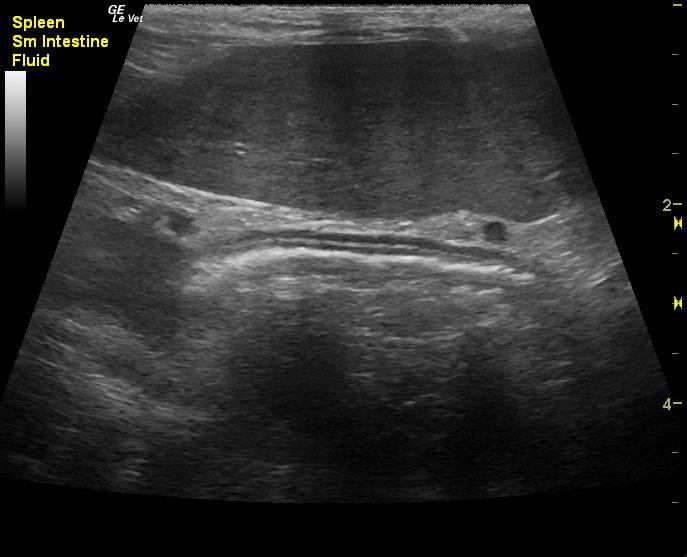

A 15-year-old neutered male DSH cat was presented for evaluation of polyphagia, weight loss, and severe splenomegaly. Abnormalities on CBC and serum biochemistry included leukocytosis, mild hypoalbuminemia, and an elevated BUN 42.